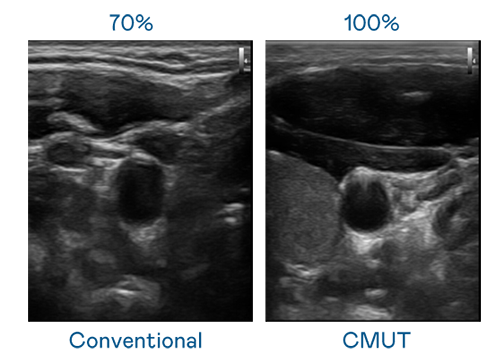

CMUT 技术是一种用电容式微机电元件来产生超音波讯号的技术。与传统 PZT 压电式技术相比,CMUT 频宽增加 30%,更宽频的超音波讯号让影像解析度大幅提升,是实现高影像品质医疗超音波扫描、促进精准医疗发展的关键技术。

大频宽带来超清晰影像

超音波影像的解析度高低,首先取决于探头能发出的讯号频宽。米兰·(milantiyu) CMUT 可提供高清晰的超音波讯号,提供高频宽、高灵敏度、影像纹理细节更高的超音波影像,协助医护人员缩短影像判读时间及利用精准的医疗影像进行诊断。